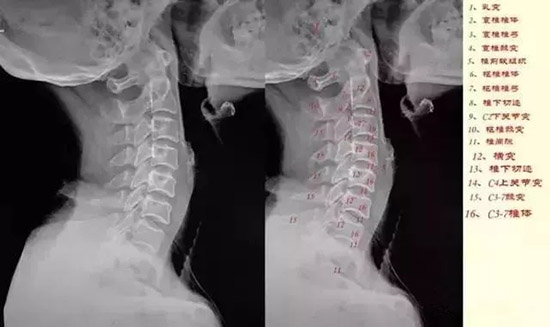

颈椎侧位颈椎侧位片可以观察椎体前缘连线形成的弧度及生理曲度的变化,在正常情况下稍向前凸。观察椎体的整体形状,对比每个椎体的变化。观察每个椎体与上下椎体之间的关系。寻找椎体后缘可疑的变化。如椎体脱位。观察椎间隙及相邻椎体的边缘。

观察有无A:椎间隙变窄;

B:前缘唇样变;

C:后缘唇样变;

D:强直性脊柱炎所致的椎体融合。

①曲度的改变:颈椎变直、生理前突消失或反弯曲,除病人的投照位置、投照角度等技术因素之外,可能会有几种原因:

在侧位片,以下三种情况有临床意义:

a:一个或两个颈椎椎间小关节突呈有双影,称为双凸现象;椎根切迹呈有双影,称为双凹现象;椎体后缘呈有双影,称为双边现象,而上下颈椎却显影正常,表示其颈椎有旋转现象。

b:上部颈椎显影正常,而下部颈椎呈现双凸、双边、双凹现象;或下部正常而上部有类似的变化,表示其交界部有旋转现象。

c:颈椎的一个或两个脊椎显影正常,而其部分有双凸、双凹、双边现象,表示显影正常的颈椎有旋转现象,如全部颈脊椎的后部呈现双凸、双凹、双边现象,则为投照不当的原因,无临床意义。